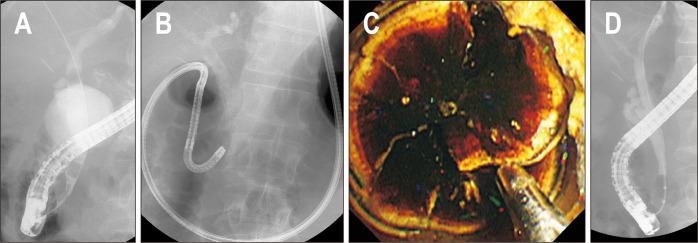

BACKGROUND/AIMS: Treatment options for difficult bile duct stones are limited. Direct peroral cholangioscopy (POC)-guided lithotripsy may be an option. A newly developed multibending (MB) ultraslim endoscope has several structural features optimized for direct POC. We evaluated the utility of direct POC using an MB ultraslim endoscope for lithotripsy in patients with difficult bile duct stones.

Twenty patients with difficult bile duct stones, in whom stone removal using conventional endoscopic methods, including mechanical lithotripsy, had failed were enrolled from March 2018 to August 2019. Direct POC-guided lithotripsy was performed by electrohydraulic lithotripsy or laser lithotripsy. The primary outcome was complete ductal clearance, defined as the retrieval of all bile duct stones after lithotripsy confirmed by balloon-occluded cholangiography and/or direct POC.

The technical success rate of direct POC was 100% (20/20), and the free-hand insertion rate was 95% (19/20). Direct POC-guided lithotripsy, attempted by electrohydraulic lithotripsy in nine patients (45%) and laser lithotripsy in 11 patients (55%), was successful in 95% (19/20) of the patients. Complete ductal clearance after direct POC-guided lithotripsy was achieved in 95% (19/20) of patients. Patients required a median of 2 (range, 1-3) endoscopic retrograde cholangiopancreatography sessions for complete stone removal. Adverse event was observed in one patient (5%) with hemobilia and was treated conservatively.